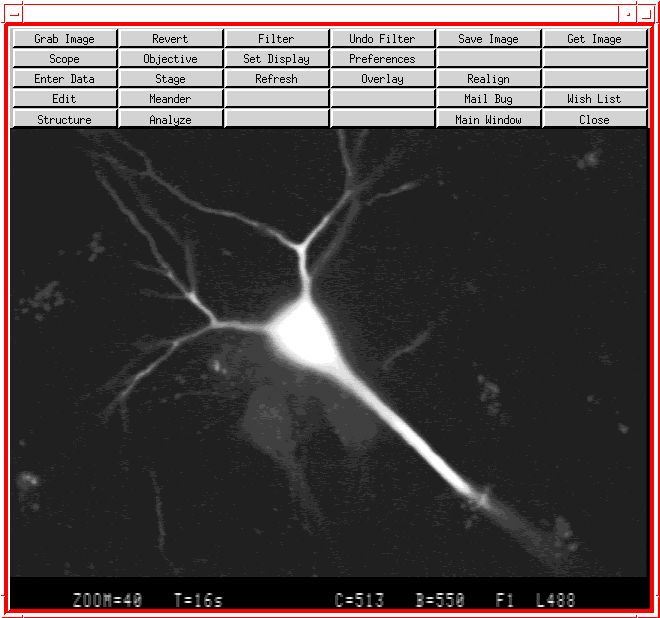

This is a picture is a brain cell from primate tissue, loaded with a special dye so that the fibers and processes on the cell body can be seen. Imaging is done on a Zeiss laser

confocal microscope. Successive images of the cell are captured until the cell can be described and visualized three-dimensionally. The image is captured by A/UX programs written in C

and in X. The laser microscope is controlled by the A/UX programs. The A/UX system acts as a video and microscope server so multiple networked X workstations such as Macintoshes running

A/UX or MacX can execute these programs and examine brain tissue.